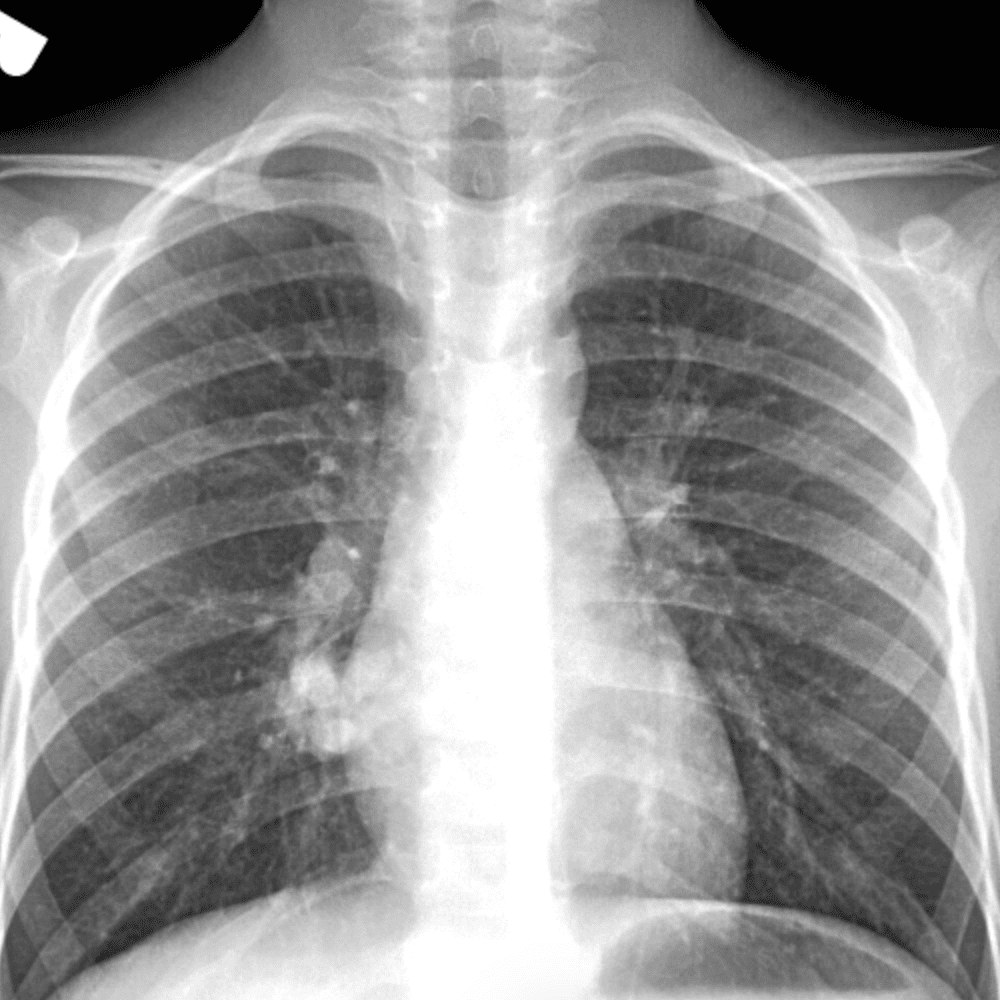

Peds Chest

Practice

Simulates call by including subtle or difficult cases and some normals.

50 cases